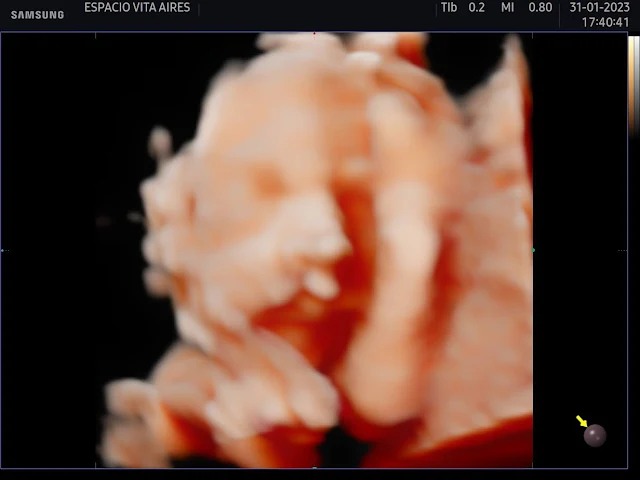

¿Quiénes somos, qué fuimos, qué seremos?

Se conjugan en la ansiedad del alumbramiento.

Comenzar a nacer ya ha sido:

un nombre, una identidad, un proyecto.

Al encuentro...

de las artes, de la música, del sentimiento.

En la maternidad dolorida que se repara

el amor se manifiesta por completo:

es la entrega cotidiana del cuidado

es mi voz que con palabras remedo;

el cariño cotidiano de esperarte,

de acompañar el desvelo.

Verte crecer dentro del vientre

anidada en las entrañas; verte nacer anhelo.

Acariciarte diminuta…

ante el mágico momento asoma un pequeño ego.

Milagrosa creación que deja mi voz trunca,

vivir presente manifiesto. Es mi vida es la tuya y el deseo,

Son los años venideros, el pasado…

tu futuro y los nuestros.